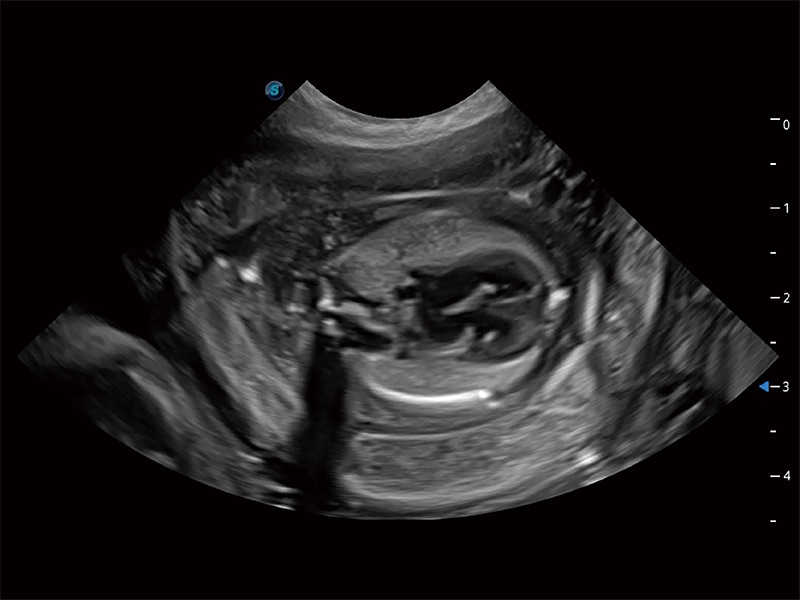

动物是人类最亲密的朋友和最值得信赖的伙伴。环球UG官网也一直致力于探索动物专用的超声影像解决方案。全新推出的ProPet系列,是环球UG官网在动物超声影像智能化、专业化、精准化的一次跨越式革新。动物不能用言语来表述自己的不适,通过超声影像,ProPet系列搭建了动物医生与不同物种沟通的“桥梁”,为动物医生注入了“治愈之力”。 ProPet 80 是环球UG官网匠心打造的一款高端动物专用彩超,采用性能卓越的全新硬件架构,极大提升超声系统的运行效率和数据处理能力,帮助动物医生从容应对日益增多的挑战性病例和日益多样化的临床需求。

高性能和先进的临床应用工具可以为动物医生提供临床信心。ProPet 80 搭载了先进的腹部和浅表应用工具,帮助医生在日常临床实践中发挥前所未有的作用。

ProPet 80 全新的动物超声智能软件和丰富的探头群,为动物医生提供了高清晰度和精细分辨率的图像,无论在宠物、马科、畜牧还是实验室动物等应用中都可以轻松应对,为您的日常工作带来满意的体验。